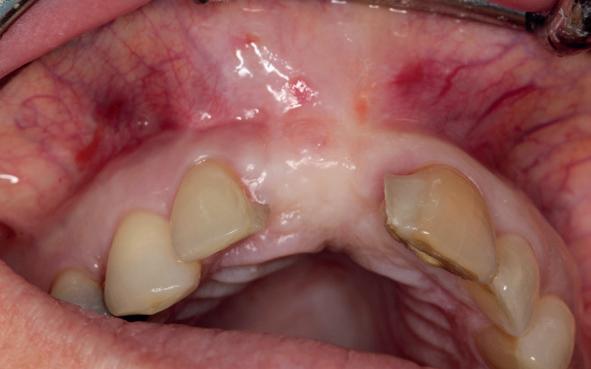

Er werd meer bekend over de gedragingen van het bot rond de “microgap” en daarmee kwam er meer begrip over hoe een implantaat goed te plaatsen in de esthetische zone. In het midden van de jaren negentig kwam daar de kennis bij hoe, op een verantwoorde manier en met behulp van guided-bone-regeneration, een implantaat in de esthetische zone te plaatsen (afbeelding 6-10).

Van vooral functionaliteit verschoof de indicatie naar esthetiek. De zachteweefselchirurgie en vaak voorbehandeling van zachte weefsels voor implantologie kreeg veel meer aandacht (afbeelding 11-14).